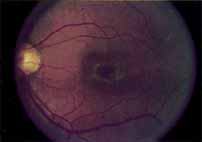

During the early stage of the dystrophy, when patients demonstrate a slight-to-moderate decrease in visual acuity and minimal color defects, there are minor or no visible fundus abnormalities. At most, the foveal reflex may be absent and there may be some increased granularity of the retinal pigment epithelium in the macula. Later, there is a decrease of visual acuity to the 20/400 range, oval atrophy of the macular retinal pigment epithelium (“beaten bronze” atrophy), and associated choroidal atrophy (Fig. 3). A characteristic bull's-eye maculopathy, similar to that seen in patients with chloroquine retinopathy, may also be seen.90 Photophobia, occasional nyctalopia, incomplete-to-complete color defects, and a central scotoma are often present. The symmetry of the process in both eyes is remarkable.